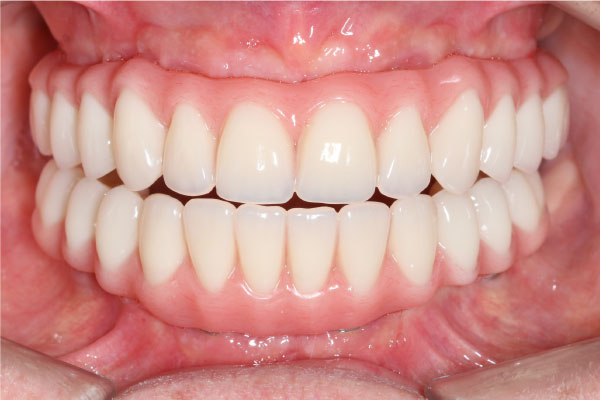

Имплантация зубов: фото "До" и "После"

Фото ДО

Фото ПОСЛЕ

Наведите для просмотра

All-on-4